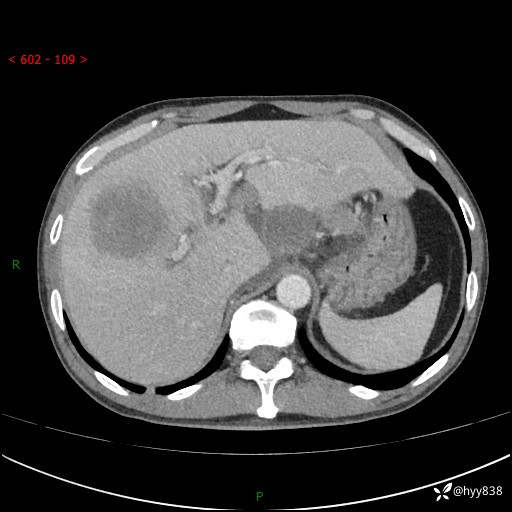

上腹部CT平扫+增强(两期)